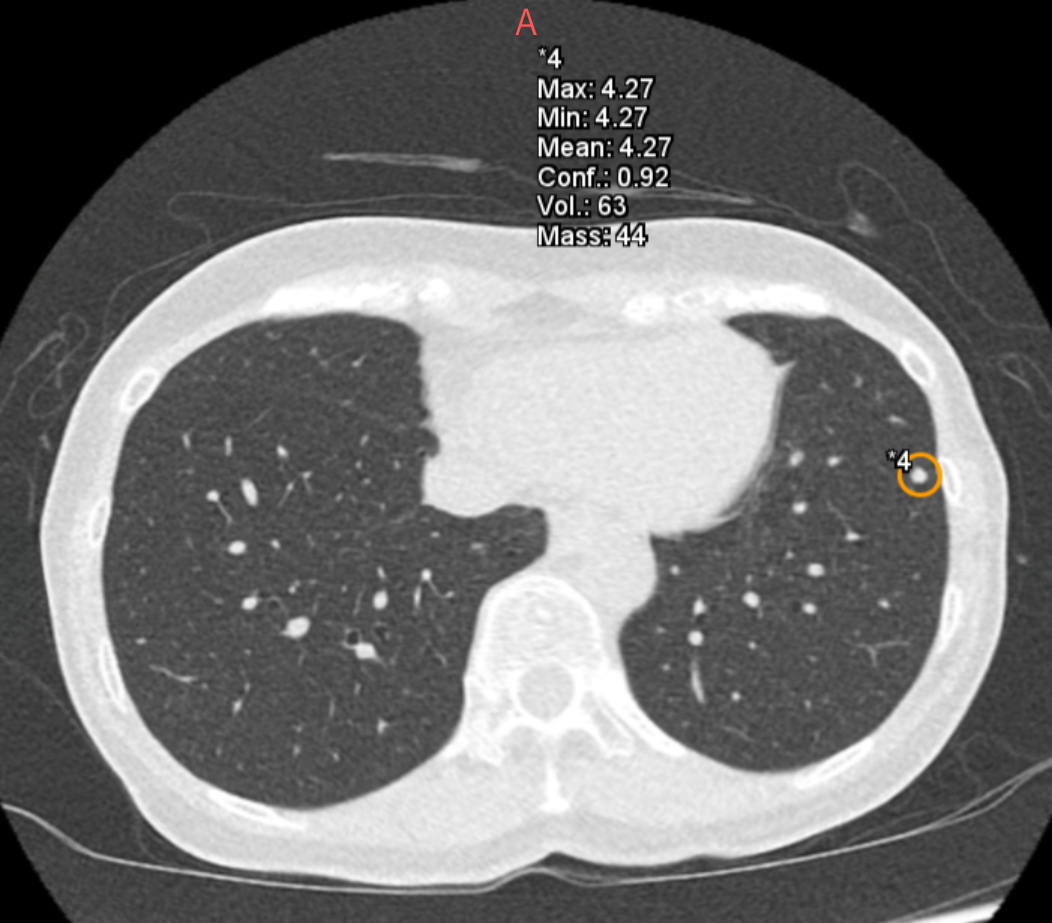

また、胸部X線AI「Plus.CXR」では著者が通常は指摘できない、径5mm前後の比較的小さな病変を指摘できます。

加えて、肺門部周囲の太い血管陰影とシルエットが明瞭に存在する淡い透過性の低下部を指摘することができました。これらは、十分な集中力で画像を参照していない場合見落とす可能性が高い所見だと思料されます(図1,2,3)。